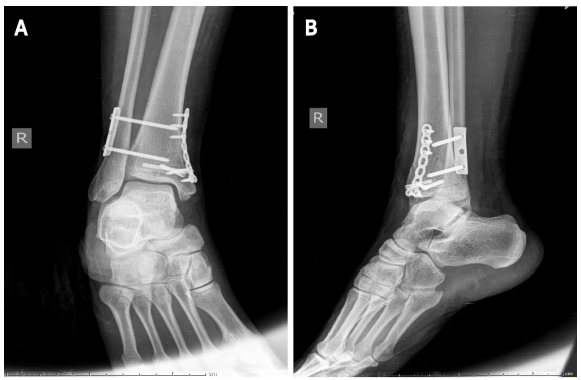

图片

图2:A:踝关节和小腿的CT正面图(箭头);B:踝关节CT扫描(箭头);C:踝关节的矢状位MRI(箭头);D:踝关节的横断面MRI(箭头);A和B:CT显示腓骨近端骨折、下胫腓关节分离、内踝骨折累及后踝(箭头);C和D:MRI显示胫腓前下韧带和距腓前韧带断裂(箭头)。